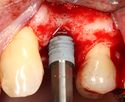

الجراحات الرئيسية

يتم اجراء جراحة الأسنان في العيادة تحت ظروف معقمة، من قبل طبيب أسنان متخصص في زراعة الأسنان و/أو جراحة الفم والفك. يتم تخدير المريض بواسطة حقنة بمخدر موضعي في منطقة دواعم السن، كما هو الحال في علاجات الأسنان العادية (في بعض الأحيان هناك حاجة بتوسيع نطاق التخدير، وفقاً لموقع الغرسات).

اذا كان العظم على استعداد لتلقي الزرع (أحيانا بعد سلسلة علاجات مسبقة)، يمكن البدء بعملية زرع الاسنان. يتم تثبيت المسامير المعدنية اللولبيه براغي، بعظم الفك. في سلسلة اخرى من العلاجات بعد فترة من ادخال البراغي، تبدا عمليات اعادة البناء عن طريق أخذ القياسات وانشاء التاج/الجسر. عندما يدور الحديث عن فترة الانتظار بين تركيب الغرسات وبين تنفيذ الاستبناء النهائي، فان هنالك اكثر من نهج واحد. النهج المتبع غالبا هو الانتظار لمدة 6 أسابيع على الأقل حتى تلتئم الانسجة، وأحيانا تصل فترة الانتظار لعدة شهور.